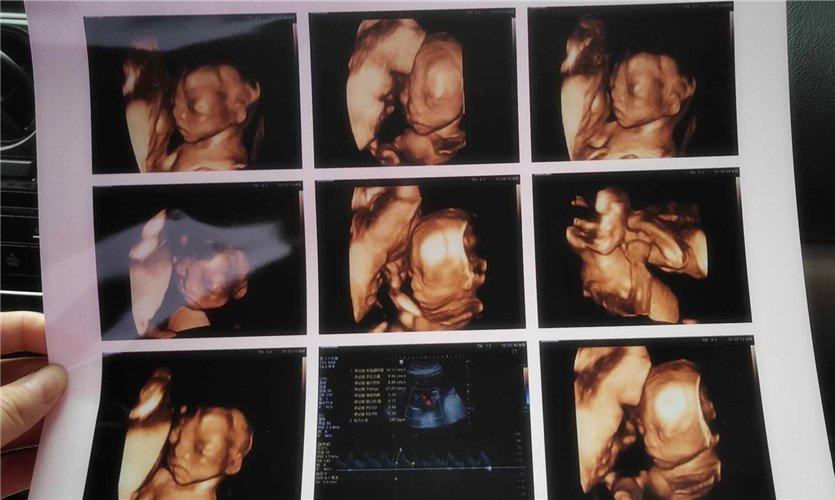

四維彩超是一種先進(jìn)的醫(yī)學(xué)影像技術(shù),通過實時觀察胎兒在母體內(nèi)的活動情況,為醫(yī)生提供了豐富的診斷信息,在四維彩超下,我們可以清晰地觀察到胎兒的蛋蛋(睪丸)的形態(tài)、位置和大小等特征,胎兒蛋蛋是男性生殖系統(tǒng)的重要組成部分,對于胎兒的生長發(fā)育具有重要意義。

在四維彩超下,胎兒蛋蛋呈現(xiàn)出特定的形態(tài)和外觀,通常情況下,胎兒蛋蛋呈現(xiàn)出圓形或橢圓形,表面光滑,內(nèi)部回聲均勻,隨著胎兒的發(fā)育,蛋蛋會逐漸增大,并呈現(xiàn)出明顯的性別特征,醫(yī)生可以通過四維彩超技術(shù),對胎兒蛋蛋的大小、形態(tài)和位置進(jìn)行評估,以判斷胎兒生殖系統(tǒng)的健康狀況。

胎兒蛋蛋的發(fā)育是一個復(fù)雜的過程,受到多種因素的影響,在胎兒發(fā)育的早期階段,蛋蛋位于腹腔內(nèi),隨著胎兒的生長發(fā)育,蛋蛋逐漸下降至陰囊,這個過程受到激素、遺傳和環(huán)境等多種因素的影響,在四維彩超的觀測下,我們可以實時了解胎兒蛋蛋的發(fā)育過程,及時發(fā)現(xiàn)異常情況并采取相應(yīng)的治療措施。